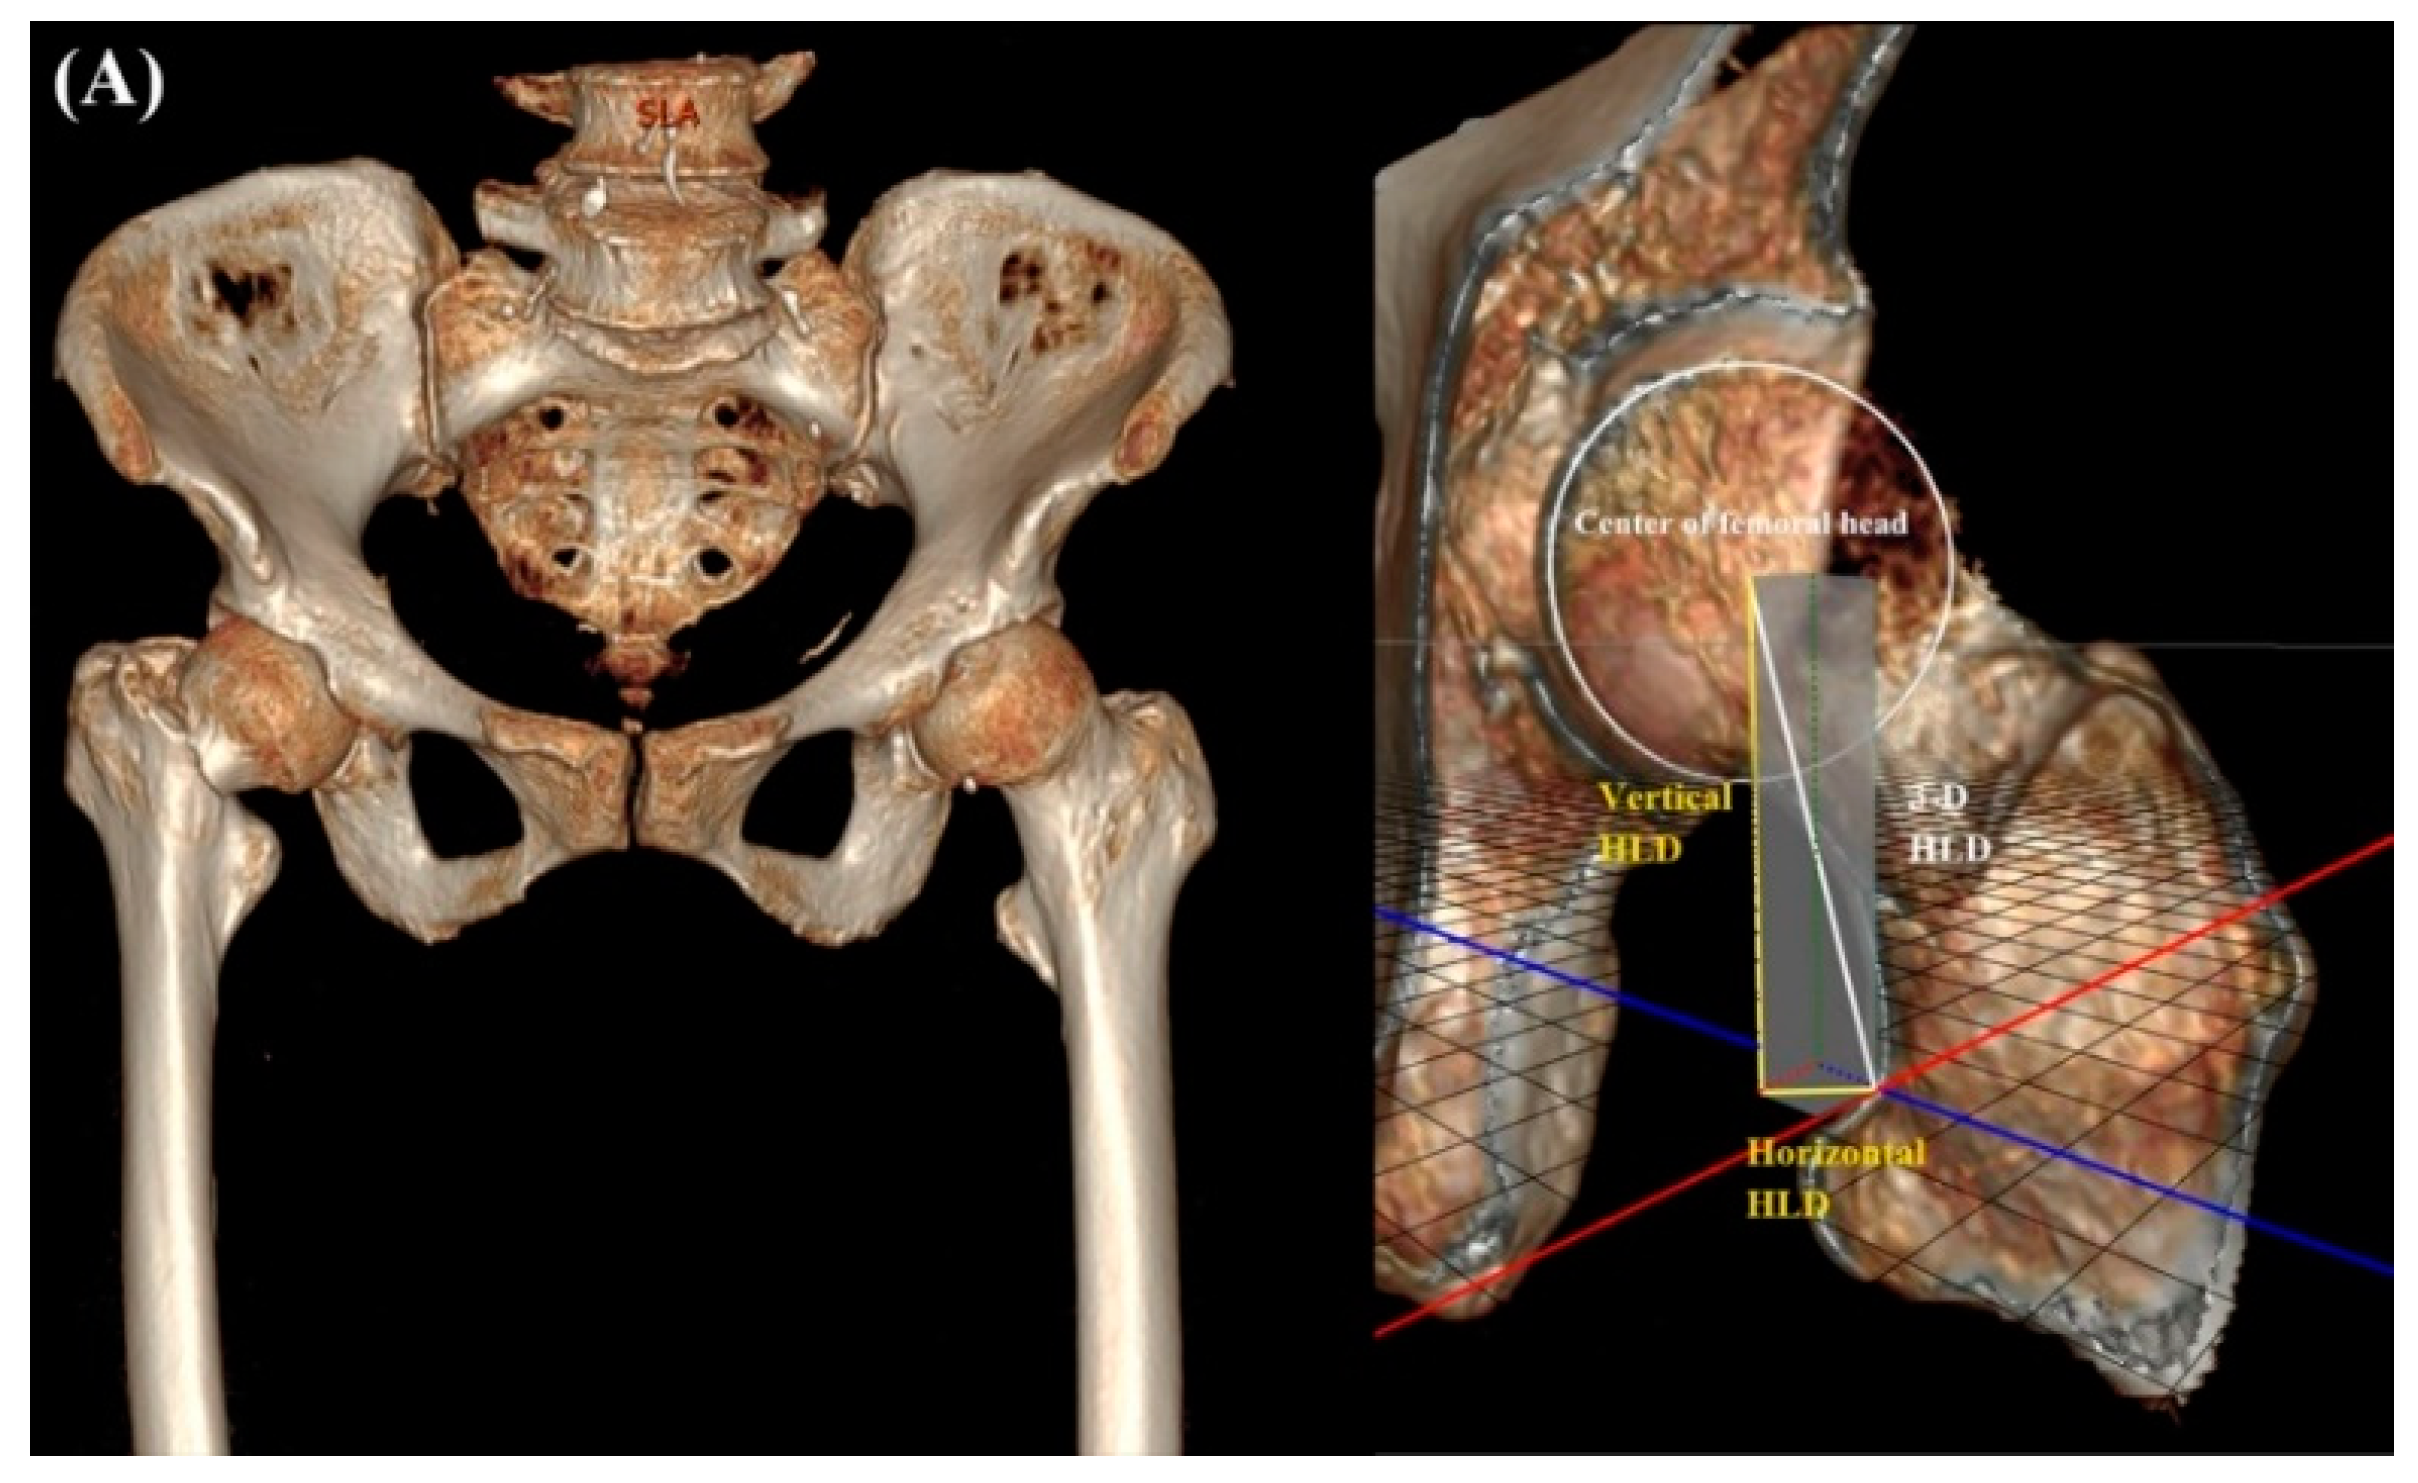

| 3-D HLD | - | 45.9 ± 3.6 | N/A |